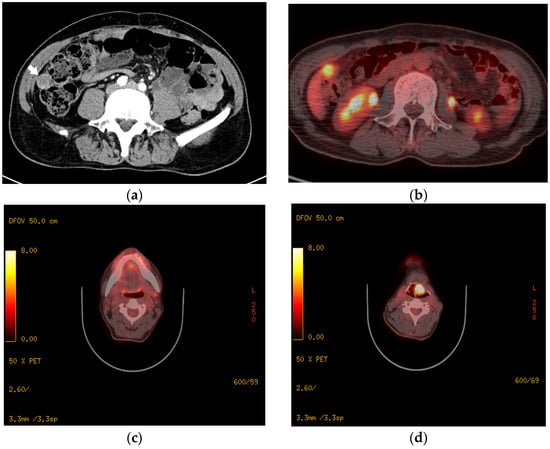

Extramedullary haematopoiesis (EMH) refers to haematopoietic proliferation outside the bone marrow, most often arising as a compensatory response to ineffective marrow function in chronic anaemias and myeloid neoplasms, particularly myelofibrosis and other myeloproliferative neoplasms. While the liver and spleen are typical sites, renal involvement remains particularly uncommon and may mimic infiltrative malignancy or infection on cross-sectional imaging. We report a 35-year-old woman with biopsy-proven grade 2 myelofibrosis who presented with constitutional symptoms, namely asthenia, progressive weight loss, and intermittent fever, in the setting of pancytopenia. Contrast-enhanced CT demonstrated bilateral thoracic paravertebral and presacral soft-tissue masses, with left peripelvic/pelvicalyceal infiltration, raising concern for infiltrative malignancy or infection. [18F]-FDG-PET/CT showed low-grade uptake in the paravertebral and presacral lesions, while the renal lesion remained indeterminate because of adjacent urinary tracer activity. Given the haemorrhagic risk of renal biopsy in a cytopenic patient, [99mTc]-sulphur colloid scintigraphy with SPECT/CT was performed and demonstrated concordant tracer uptake in all lesions, supporting multifocal EMH. After disease-directed treatment, follow-up CT at 12 months showed marked regression of the renal and other EMH lesions. This case highlights renal peripelvic EMH as a rare imaging pitfall and underscores the value of multimodality imaging when biopsy is high risk. Full article